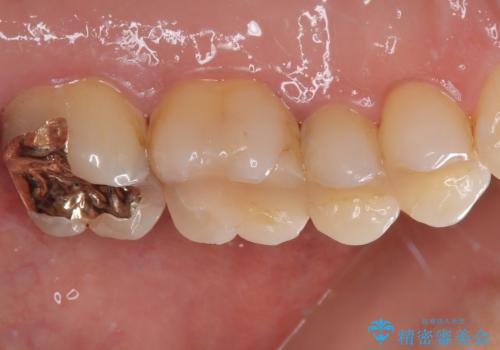

- 奥歯がかけてしまい、しみるようになったとのことで来院された患者様です。

上顎奥の粘膜に近い部分で、つめものの下には大きく虫歯が広がっていました。

虫歯をしっかりと取り除き、ゴールドインレーにて修復することとしました。